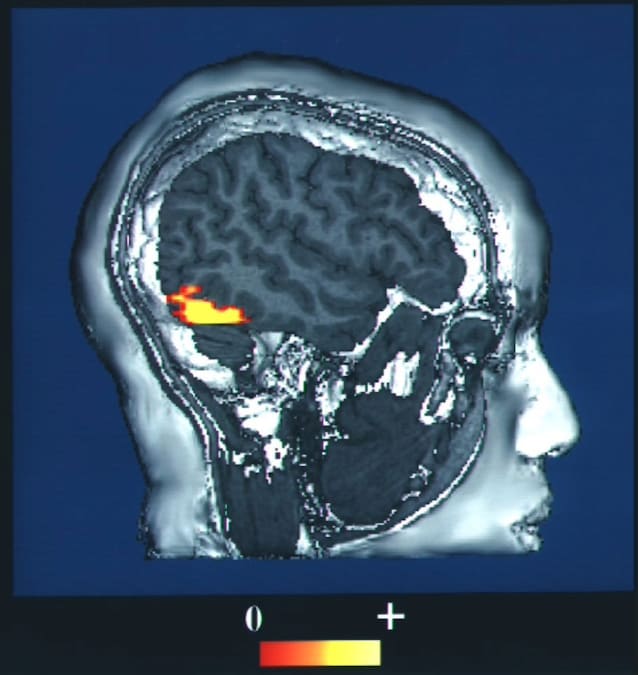

Even if we are not aware of it, every time we observe a familiar face our brain carries out exactly this operation: some areas of the temporal cortex identify what we are observing as a facewhile other regions, belonging to limbic systemthey give it an emotional meaning. Thanks to specific neuronal connections (real “roads of the brain”), information relating to physiognomic characteristics is integrated with affective ones, allowing us to recognize that the face in front of us does not belong to just any person.

In patients with Capgras syndrome, these connections between the temporal and limbic regions could be compromisedfor example following a cerebral stroke or a neurodegenerative pathology, causing the inability to associate the face of a person known for his sentimental value. In short, those who suffer from Capgras syndrome are able to see a friend or family member, but are no longer able to feel it as such, mistakenly mistaking him for a lookalike.